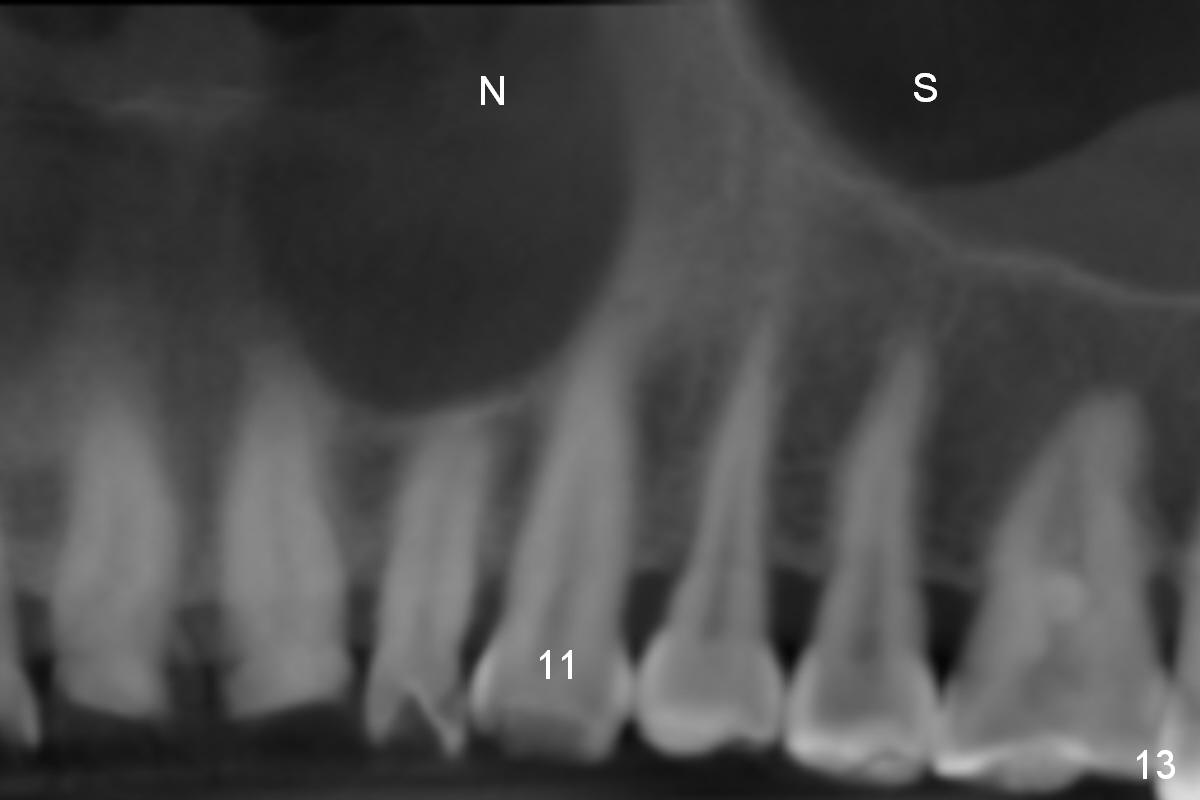

The ridge looks wide clinically 4 months post implant removal and socket preservation. In fact, the graft bone is soft and the ridge is narrow after incision. It appears that an angled 1 piece implant is an indication. A 1.2 mm pilot drill is used to start osteotomy. At approximately 17 mm, the patient feels pain. The nasal floor perforates? A 2 mm osteotome is utilized to enlarge the osteotomy. At 17 mm, the osteotome is stable (Fig.1), but the nasal floor appears out of view. Review of the preop PA shows that the distance between the gingival margin and the nasal floor (arrowheads) is ~22 mm (Fig.2). It should be safe and necessary to place a 3x20 mm 1-piece implant with 15° angulation. Insertion torque is between 40 and 45 Ncm.

Eight months postop, the patient returns for #11 restoration. She reports no problem at #11, while there is light tenderness with a 2-piece implant (4.5x20 mm) at #6 at night (Fig.10, a portion of panoramic X-ray). Clinical exam reveals no abnormality at #6. Although the implant at #11 is buccally placed, there is no buccal plate atrophy (Fig.6,7). In fact the 20 mm 1-piece implant is placed in the bone (septum) between the nasal cavity (Fig.10 pink dashed line; Fig.13 (CBCT (52 year-old lady) N) and the maxillary sinus (yellow dashed line, S). In fact the apparent nasal floor indicated as arrowheads in Fig.2 and 10 is the horizontal plate of the palatine bone (hard palate)! Therefore there is no nasal floor perforation in this case. A long implant is indicated in the upper canine.